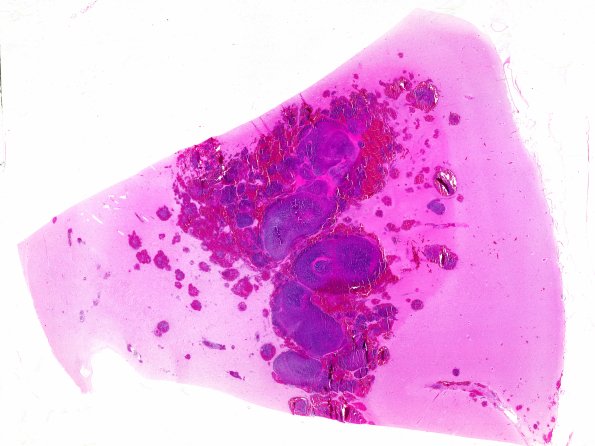

Granulocytic Sarcoma

1B1 (Case 1) E WM

A whole mount of the temporal lobe lesion shows multiple basophilic elements with delicate rims of hemorrhage. (H&E)